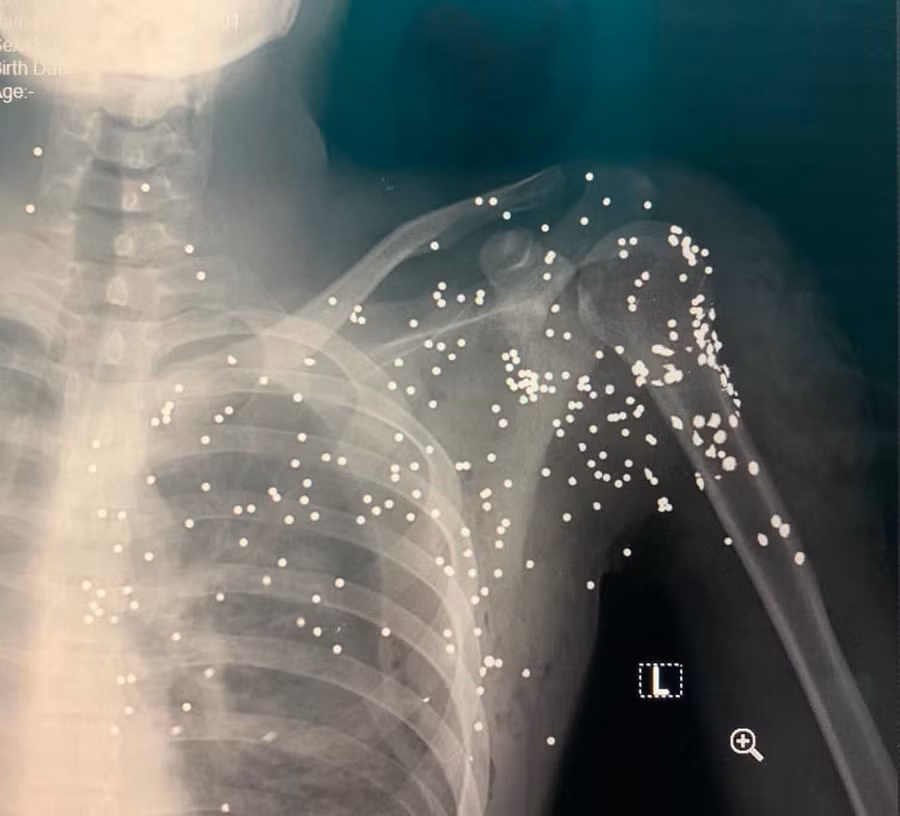

Sau khi nổ súng bắn anh H. đối tượng đã nhanh chóng rời khỏi hiện trường. Vụ việc khiến anh H. bị nhiều viên đạn súng hoa cải găm vào vùng bả vai, bị trọng thương và được đưa đi cấp cứu tại Bệnh viện Đa khoa tỉnh Thái Bình trong tình trạng đa chấn thương.

Tối cùng ngày, nạn nhân được đưa lên cấp cứu tại Bệnh viện Hữu nghị Việt Đức (Hà Nội). Sau khi sự việc xảy ra, cơ quan chức năng đã nhanh chóng triển khai các lực lượng nghiệp vụ tiến hành điều tra, vây bắt hung thủ gây ra vụ nổ súng.